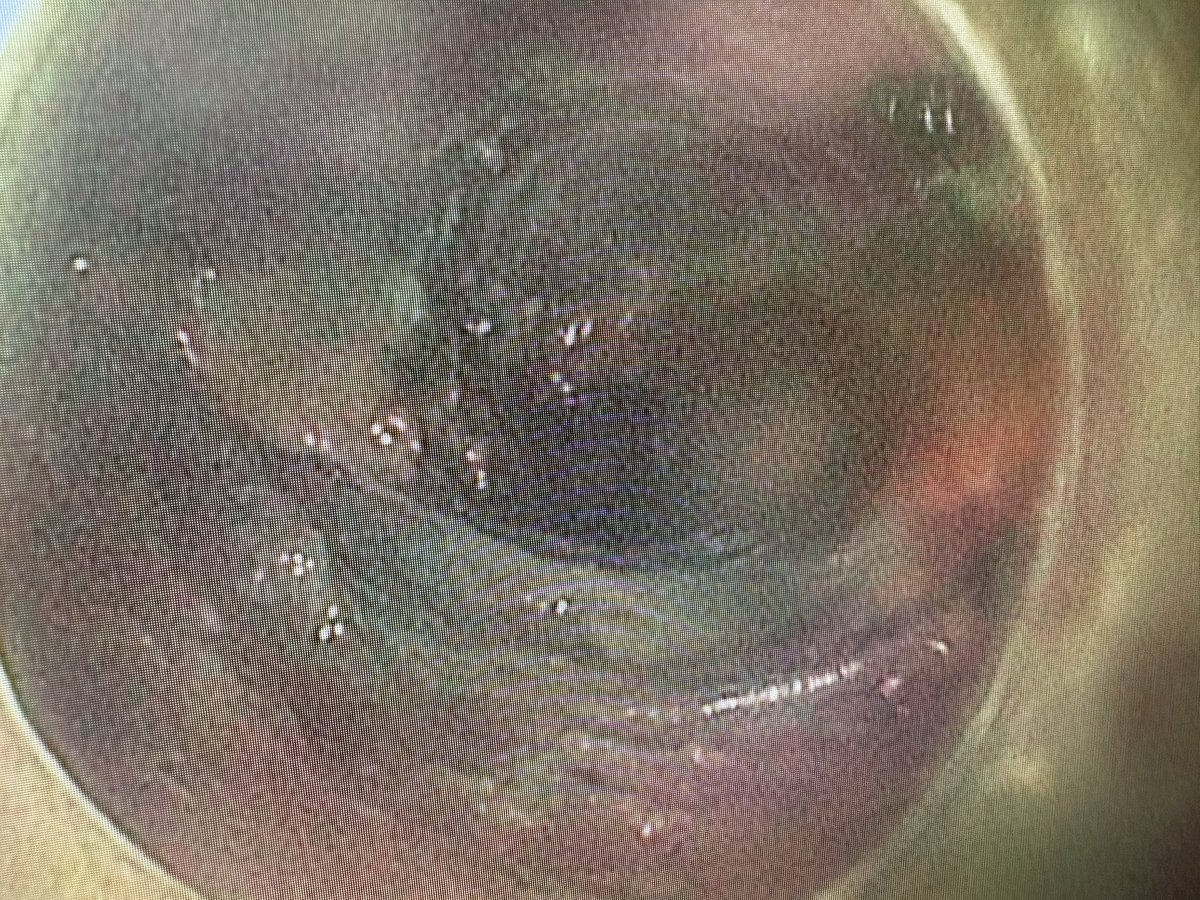

Delighted to share a MAJOR milestone in minimally invasive cancer treatment. We just completed the *first* Pharyngeal ESD in North America at @KingstonHSC . Huge thanks to the GI endoscopy team, @QueensuDOM, @SEAMOKingston for your endless support